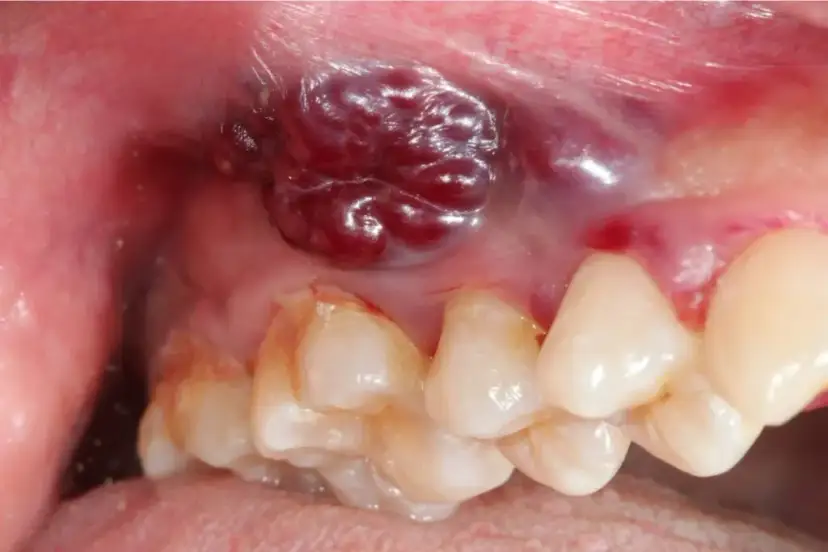

Rak jamy ustnej: poznaj wczesne objawy i sygnały alarmowe. Dowiedz się, jak rozpoznać niepokojące zmiany i dlaczego szybka diagnostyka ratuje życie. Sprawdź nasz poradnik.